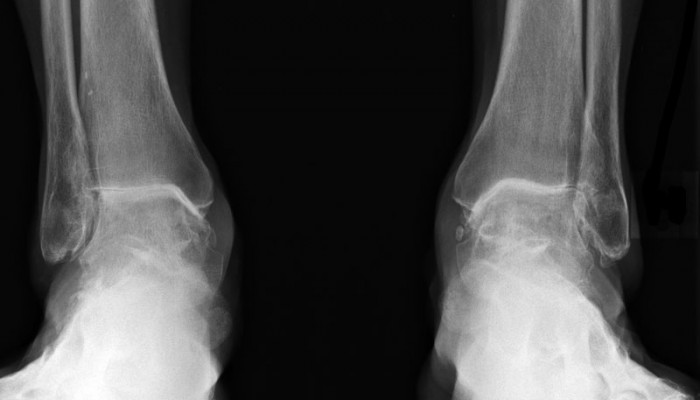

Вторая степень ДОА диагностируется как визуально, так и на рентгене. При наружном осмотре заметно увеличение сустава, его движение ограничено, хорошо слышен хруст. На рентгене диагностируется уменьшение суставной щели на 50%. Опытный врач обязательно назначит рентген в боковой проекции. На нём будет видна таранная кость. При деформирующем остеоартрозе она уплощена, а её суставная поверхность увеличена.

При дальнейшем развитии заболевания (III степень) сустав всё больше деформируется, суставная щель уменьшается. Наблюдается значительное ограничение подвижности. Попытка повернуть стопу в нужном направлении вызывает боль. Наблюдается явно выраженный субхондральный остеосклероз, разрастание костной ткани (остеофиты) сильное.

IV степень – повод обратиться в медкомиссию за получением инвалидности. Суставная щель полностью отсутствует. Костные образования (остеофиты) прочно фиксируют сустав в вынужденном положении. Деформация может дополняться подвывихом. Эпифизы составляющих сустав костей сильно уплотнены.

- Рентгена. На нём будет видно, в каком состоянии хрящ, как наклонена ось больного сустава, поражены ли близлежащие суставы. На основании картины специалист поймёт, что стало причиной начала дегенеративных процессов.